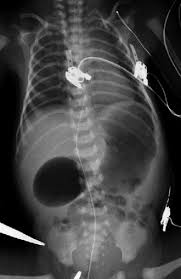

1. Neumatosis intestinal: La presencia de gas en la pared intestinal es un hallazgo clásico y altamente sugestivo de NEC.

2. Neumoperitoneo: La presencia de gas libre en la cavidad peritoneal sugiere perforación intestinal y es una indicación para intervención quirúrgica.[1][3-4]

4. Gas portal venoso: La presencia de gas en la vena porta es otro hallazgo ecográfico que puede estar presente en NEC, aunque su asociación con la necesidad de cirugía o muerte no es tan fuerte como otros hallazgos.[2][4]